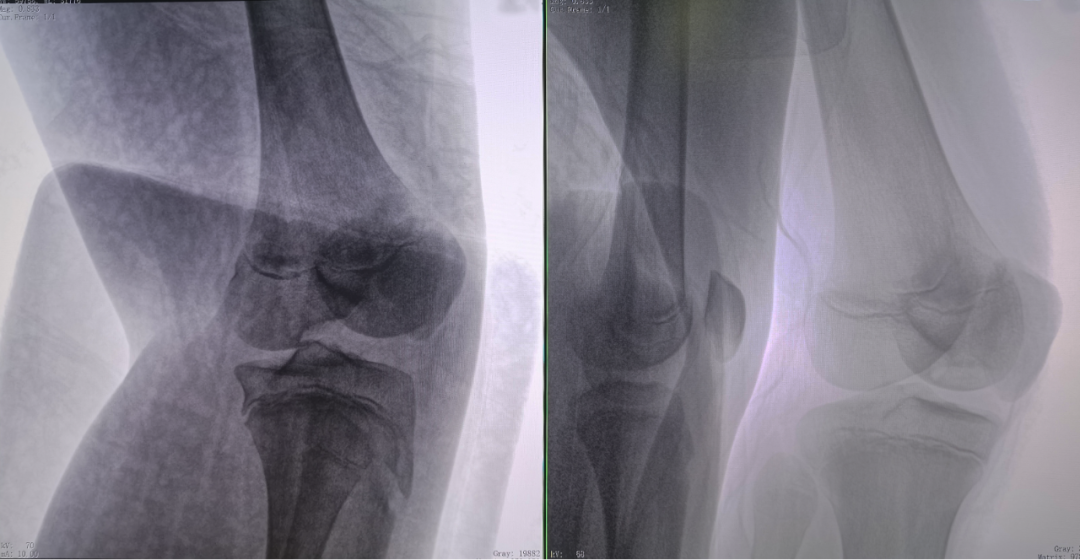

二維正側(cè)位影像

病例2 踝關(guān)節(jié)骨折復(fù)位(31歲)

在踝關(guān)節(jié)骨折復(fù)位手術(shù)中,用三維C可以更好地觀察骨折部位的復(fù)位情況:

正側(cè)位影像觀察脛腓聯(lián)合復(fù)位良好

從三維影像看,復(fù)位欠佳,貼合度不夠

二維C形臂提供的影像存在固有局限性,其成像原理是基于單一方位的投影,導(dǎo)致深部解剖結(jié)構(gòu)信息缺失,且容易受到骨骼和組織的重疊干擾,使得部分病灶難以清晰顯示,甚至被掩蓋。相比之下,三維C形臂通過三維重建技術(shù),可以獲得類似CT的斷層掃描圖像,從而解決了二維影像的重疊問題。

醫(yī)生能夠利用這些三維圖像,更直觀、更深入地分析病變,進(jìn)行全方位觀察,例如:精確評估骨折復(fù)位情況、清晰顯示內(nèi)植入物的位置及其與周圍組織的關(guān)系等。尤其在復(fù)雜骨折、脊柱手術(shù)、呼吸介入等臨床場景中,三維C形臂提供的詳細(xì)信息對手術(shù)導(dǎo)航和療效評估至關(guān)重要。